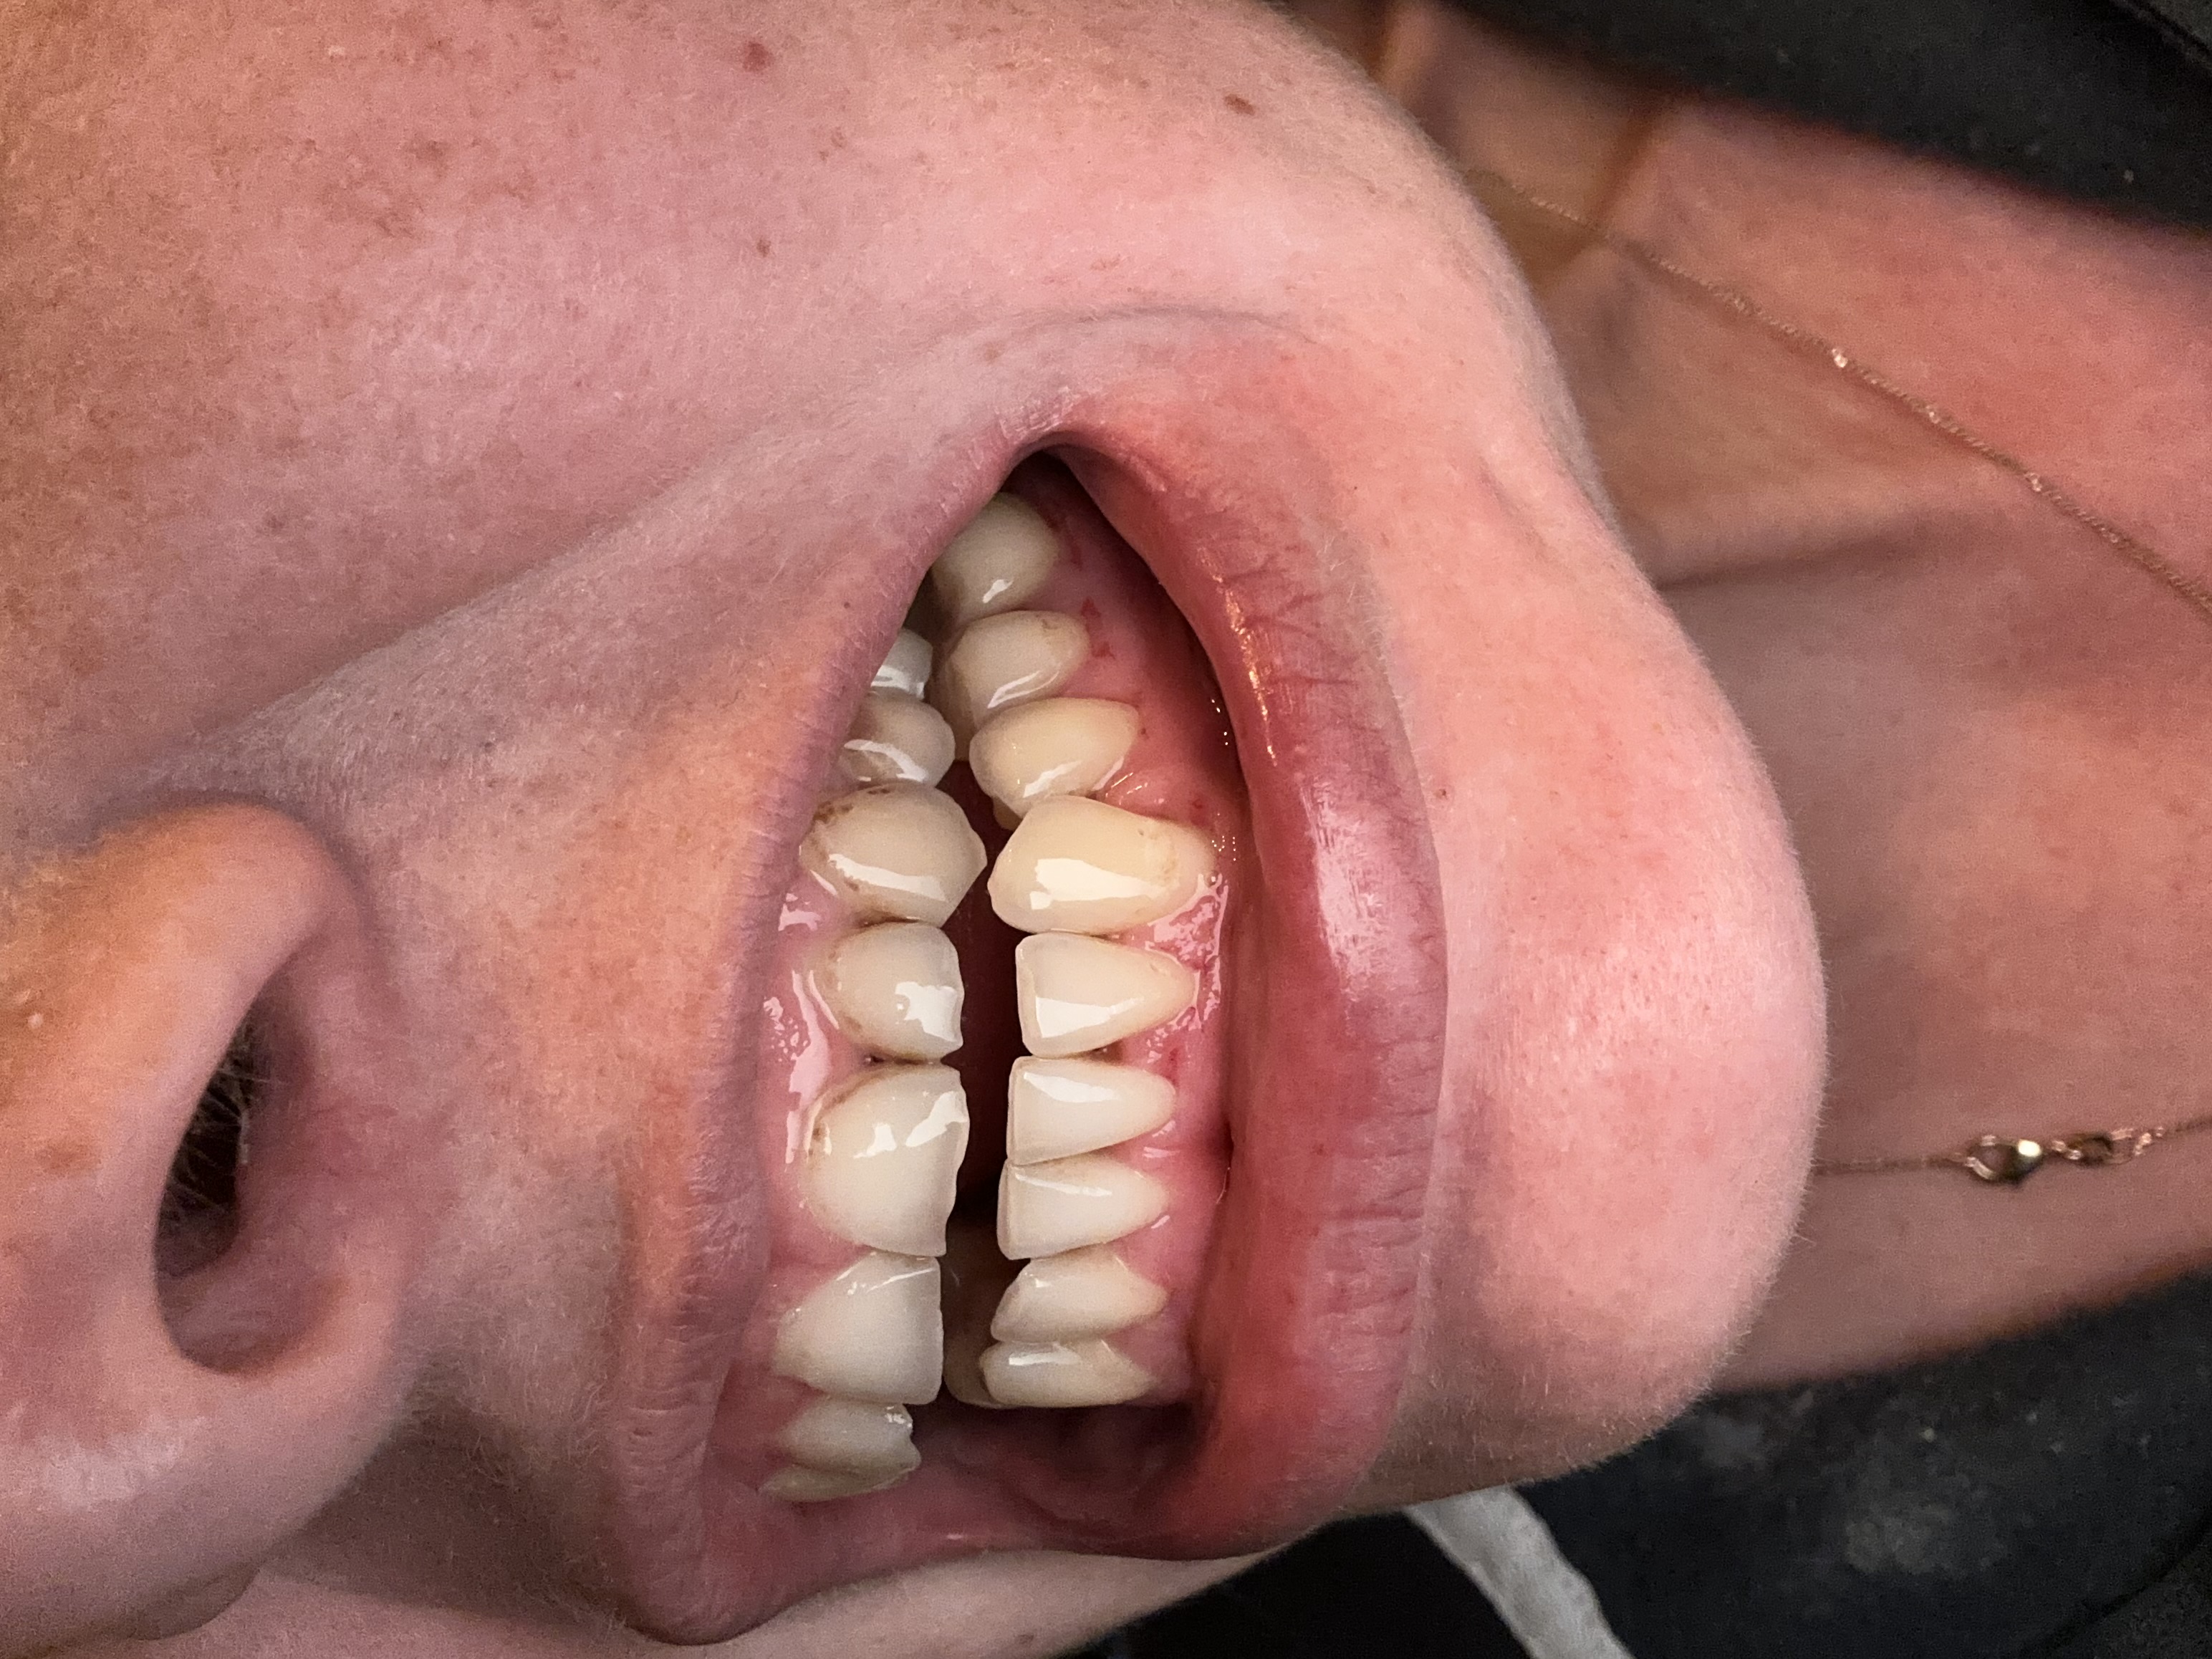

Zie foto

Deze foto is nu van nu

Zie foto’s van nu